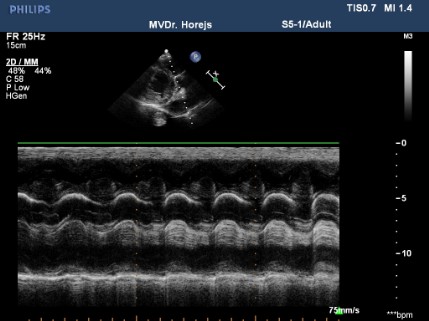

Myxomatózní degenerace mitrální chlopně